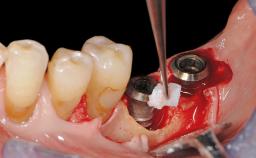

Reconstructive Treatment of a Peri-Implantitis Defect at an Implant in a Mandibular Molar Site

In this case, Mario Roccuzzo utilizes surgical bone regeneration treatment around implant 46 using a bone graft substitute and a connective tissue graft to resolve peri-implant inflammation, reduce the probing depths, and prevent further progression of disease.